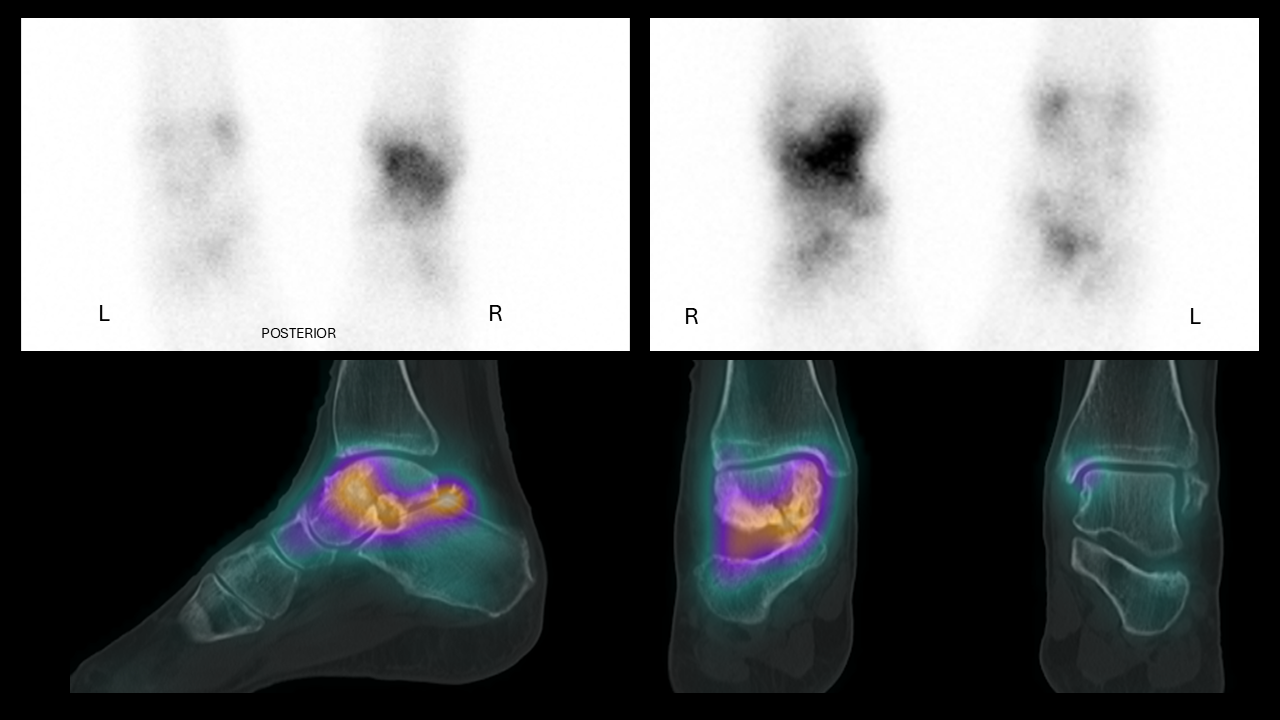

Medical imaging of the left and right feet showing posterior views, with heat maps highlighting areas of activity or concern in the middle region of both feet